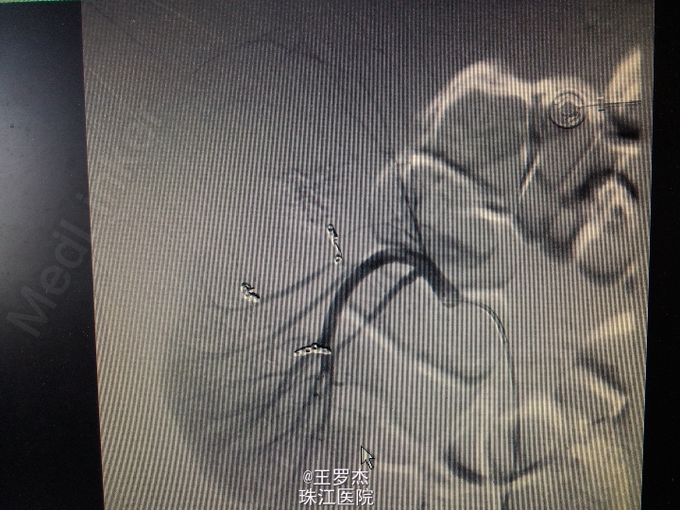

诊断治疗:右肾挫裂伤,保守治疗。3天后复查Hb89g/L,RBC2.65;复查CT提示包膜下及盆腔积血较前增多。请介入科会诊,行右肾动脉选择性栓塞。 介入:右肾挫裂伤,并上极动脉破裂出血及远端多处动静脉瘘形成,成功行超选择性病变血管栓塞术。